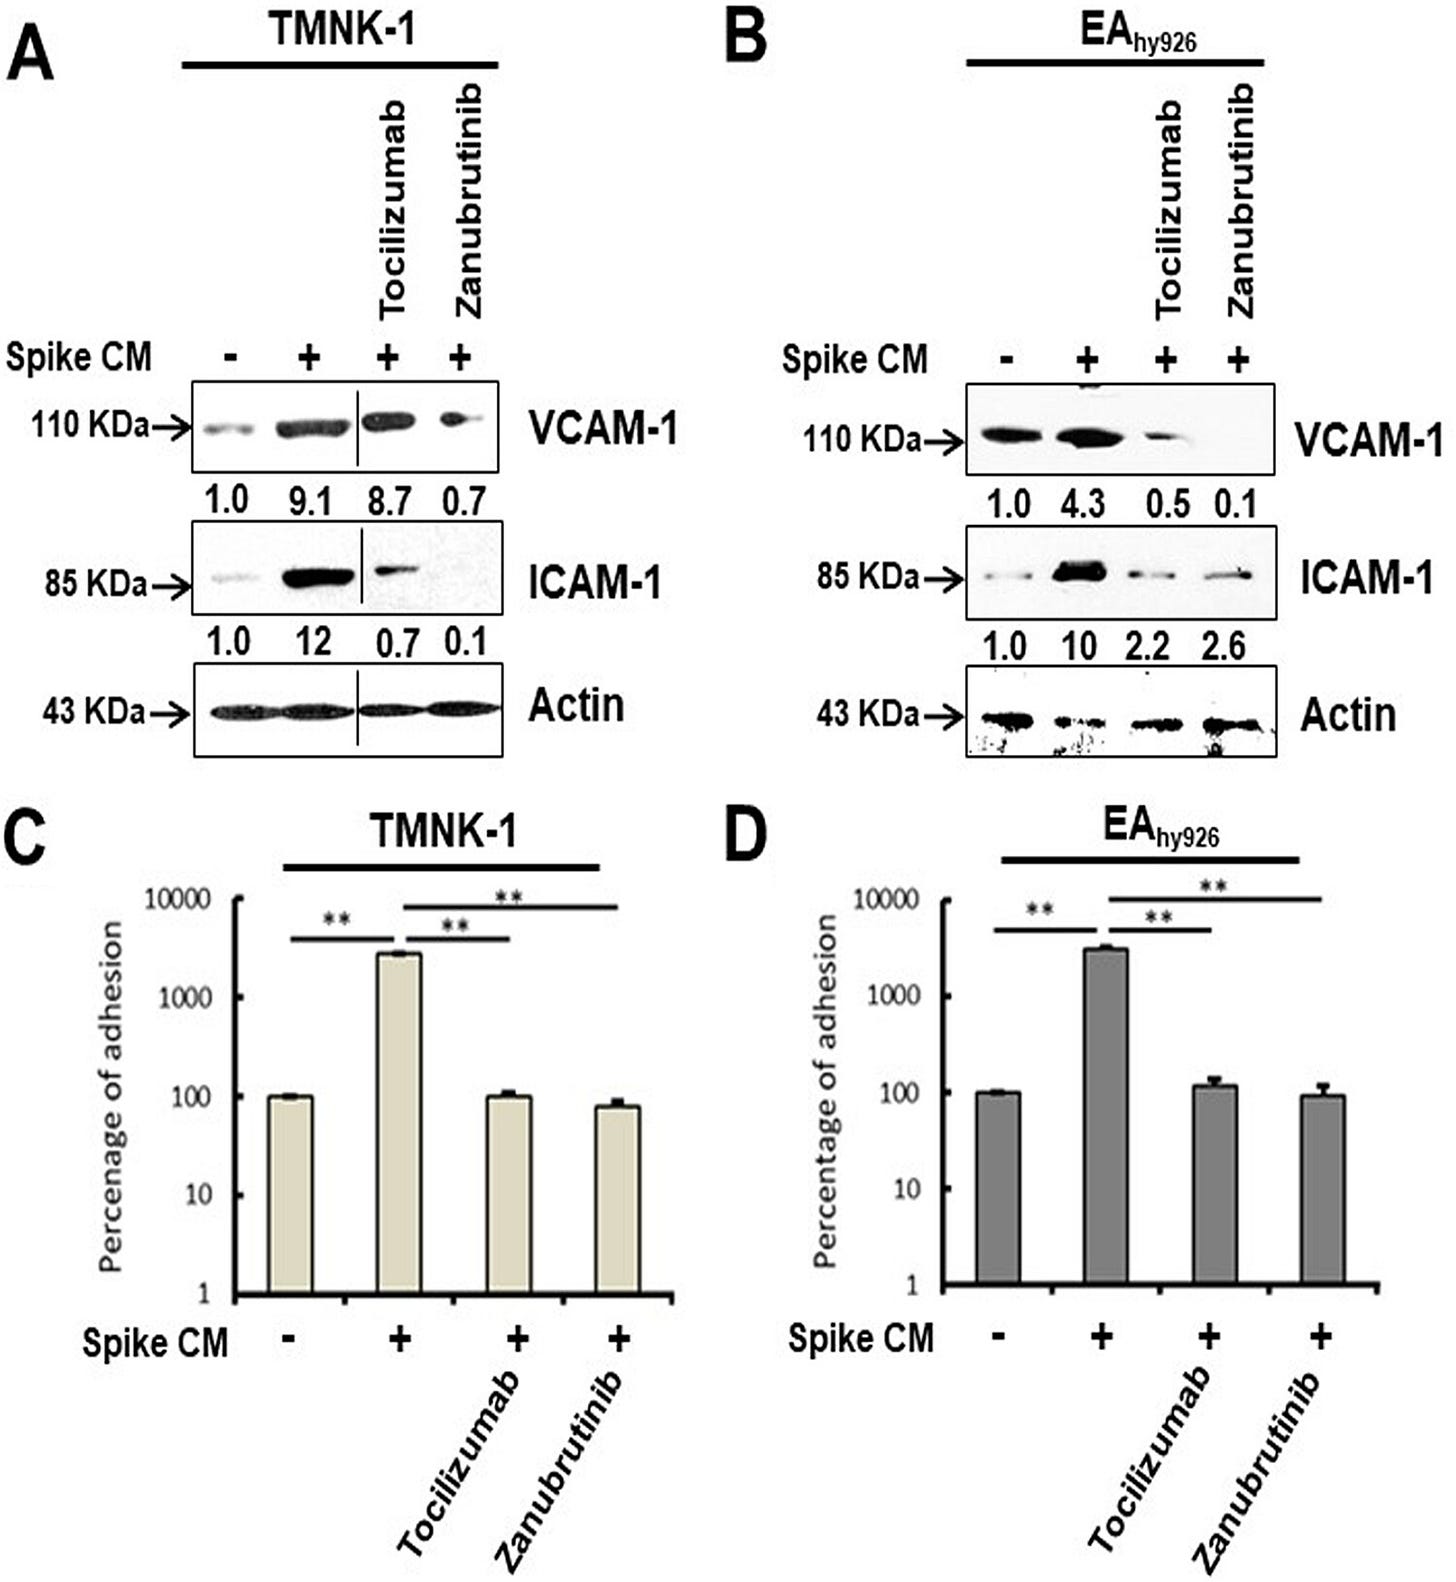

Inhibition of IL-6 trans signaling by tocilizumab and inhibition of inflammatory receptor signaling by the Bruton’s tyrosine kinase (BTK) inhibitor zanubrutinib, prior to exposure of CM to endothelial cells, inhibited p21 and p16 induction. We also observed an increase in reactive oxygen species (ROS) in A549 spike-transfected and endothelial cells exposed to spike-transfected CM. ROS generation in endothelial cell lines was reduced after treatment with tocilizumab and zanubrutinib.

This is not good at all for your cardiovascular health, and by implication for neurological health:

Cellular senescence was associated with an increased level of the endothelial adhesion molecules vascular cell adhesion molecule 1 (VCAM-1) and intercellular adhesion molecule 1 (ICAM-1), which have in vitro leukocyte attachment potential. Inhibition of senescence or SASP function prevented VCAM-1/ICAM-1 expression and leukocyte attachment. Taken together, we identified that human endothelial cells exposed to cell culture supernatant derived from SARS-CoV-2 spike protein expression displayed cellular senescence markers, leading to enhanced leukocyte adhesion.

Back to our paper on spike induced paracrine senescence. As an example of a cancer therapeutic which targets inflammatory signalling zanubrutinib is used to treat B-cell lymphomas:

The Bruton’s tyrosine kinase (BTK) inhibitor zanubrutinib is used to treat B-cell malignancies and prevents a vast range of inflammatory receptor signaling, including that by the tumor necrosis factor receptor (TNFR), IRAK, and all TLRs except TLR3 (16). Treatment of TMNK-1 and EAhy926 endothelial cells with zanubrutinib prior to exposure to spike CM caused significant attenuation in Akt and p38-MAPK phosphorylation (Fig. 5A and B).

As if BRD4 induced SASP or carcinogenesis isn’t bad enough, endothelial cell surfaces express the adhesion molecules vascular cell adhesion molecule 1 (VCAM-1) and intercellular adhesion molecule 1 (ICAM-1) in response to cytokines, contributing to leukocyte attachment and initiating vasculopathy:

Our Western blot analysis showed that both TMNK-1 and EAhy926 cells express increased levels of VCAM-1 and ICAM-1 molecules after exposure to CM from SARS-CoV-2 spike-expressing A549 cells (Fig. 7A and B). These enhanced levels of VCAM-1 and ICAM-1 were reduced after rescue from senescence following treatment with tocilizumab or zanubrutinib. To further determine whether these contrasting phenotypes are seen under physiological conditions, we assessed leukocyte adhesion using a fluorometric assay on the human monocyte cell line THP-1. A significant cellular adhesion of THP-1 cells on the surface of TMNK-1 and EAhy926 cells was detected in the presence of CM from SARS-CoV-2 spike-expressing A549 cells, in association with elevated expression of the adhesion molecules (Fig. 7C and D). The loss of leukocyte adhesion is also corroborated by the reduction of VCAM-1 and ICAM-1 after treatment with tocilizumab or zanubrutinib. These results indicate that leukocyte trafficking occurs to endothelial cells in an in vitro cellular environment, which is influenced by SARS-CoV-2 spike expression and paracrine senescence in surrounding epithelial cells.